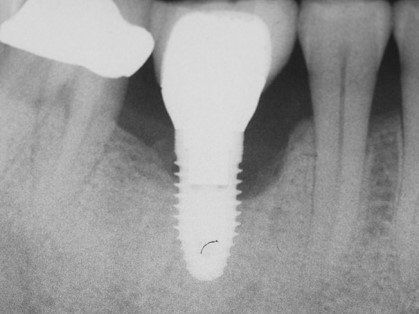

Рентгенография. Позволяет отличить периимплантный мукозит от периимплантита: при мукозите на рентгенограмме нет патологических изменений вокруг имплантата; при периимплантите видно убыль кости. Также рентген помогает определить глубину зондирования и увидеть плохое прилегание элементов протеза [14] .

![Периимплантит на рентгенограмме [18]](/pimg3/mukozit-prichini-simptomi-1A72CC.jpeg)